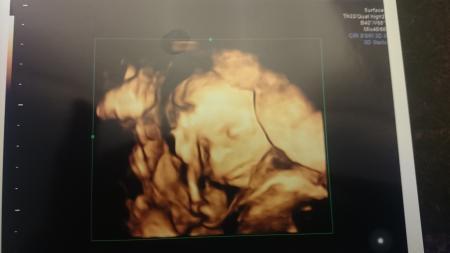

Hallo liebe Elli, Herzlich willkommen hier. Das forum ist auch echt nett und der Austausch mit allen ist toll. Glückwunsch zum Mädchen, das ist ja sehr schön und noch besser, dass es dir sehr gut geht. Schwangerschaftsbeschwerden können nämlich echt doof sein. An die Übelkeit am Anfang mag ich gar nicht zurück denken. Im Moment kann ich nur nicht gut schlafen, ansonsten kann ich mich auch nicht beschweren. Ich wünsche dir noch eine schöne Kugelzeit. Magst du uns denn mal ein Ultraschall Bild von deiner Maus zeigen? Bin neugierig. Viele liebe Grüße

Vielen Dank für die liebe Aufnahme. Die Ultraschallaufnahme ist vom 11.09. und bisher das letzte was ich habe. Lg Elli